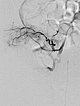

In view of massive coagulopathy prohibiting open surgery in this location and lack of improvement with drug therapy and replacement of platelets and coagulants alone, the decision was made to embolize the hypervascularized tumor. Digital subtraction angiography (DSA) shows the highly vascularized tumor supplied mainly from the right superior gluteal artery.

The tumor shows the typical tumor blush with diffuse, strong contrast enhancement on DSA after super-selective catheterization with the microcatheter.